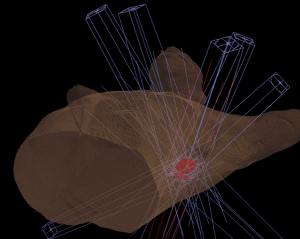

昔の二次元的な照射ではなくCTを用いて計画し(IGBT)、通常の腔内照射だけでは効果が不十分な例には組織内照射を併用することで(ハイブリッド照射)、膀胱や直腸の副作用を減らして病巣により効果の高い治療を実現しています。

前立腺癌は当院のIMRTでは約6週間(28回)の通院が必要ですが、医療圏が広いため継続した通院が困難な患者さんもおられます。当院では写真のような米粒大の線源を前立腺に留置する密封小線源治療を行っています。治療時間は3時間ほどで、入院期間は2泊3日と短く、長期間の通院が困難な方々に役立っています。また小線源・外部照射・内分泌療法を組み合わせたtrimodalityは外部照射よりも治療効果が高いです。直腸出血が稀に起こるため、その頻度をさらに減らすため小線源治療の術中にスペーサー(Hydrogel)を留置しています。このスペーサーは3ヶ月間維持され、6-12ヶ月で自然吸収されます。